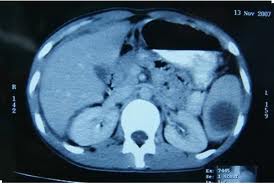

CT of abdominal abscess

The best imaging procedure for the diagnosis of abdominal abscesses is CT. 8 Ultrasonically guided fluid collection and abscess drainage are routine procedures in diagnosis and treatment of abdominal abscesses. CT and fluoroscopy with contrast often give invaluable information.